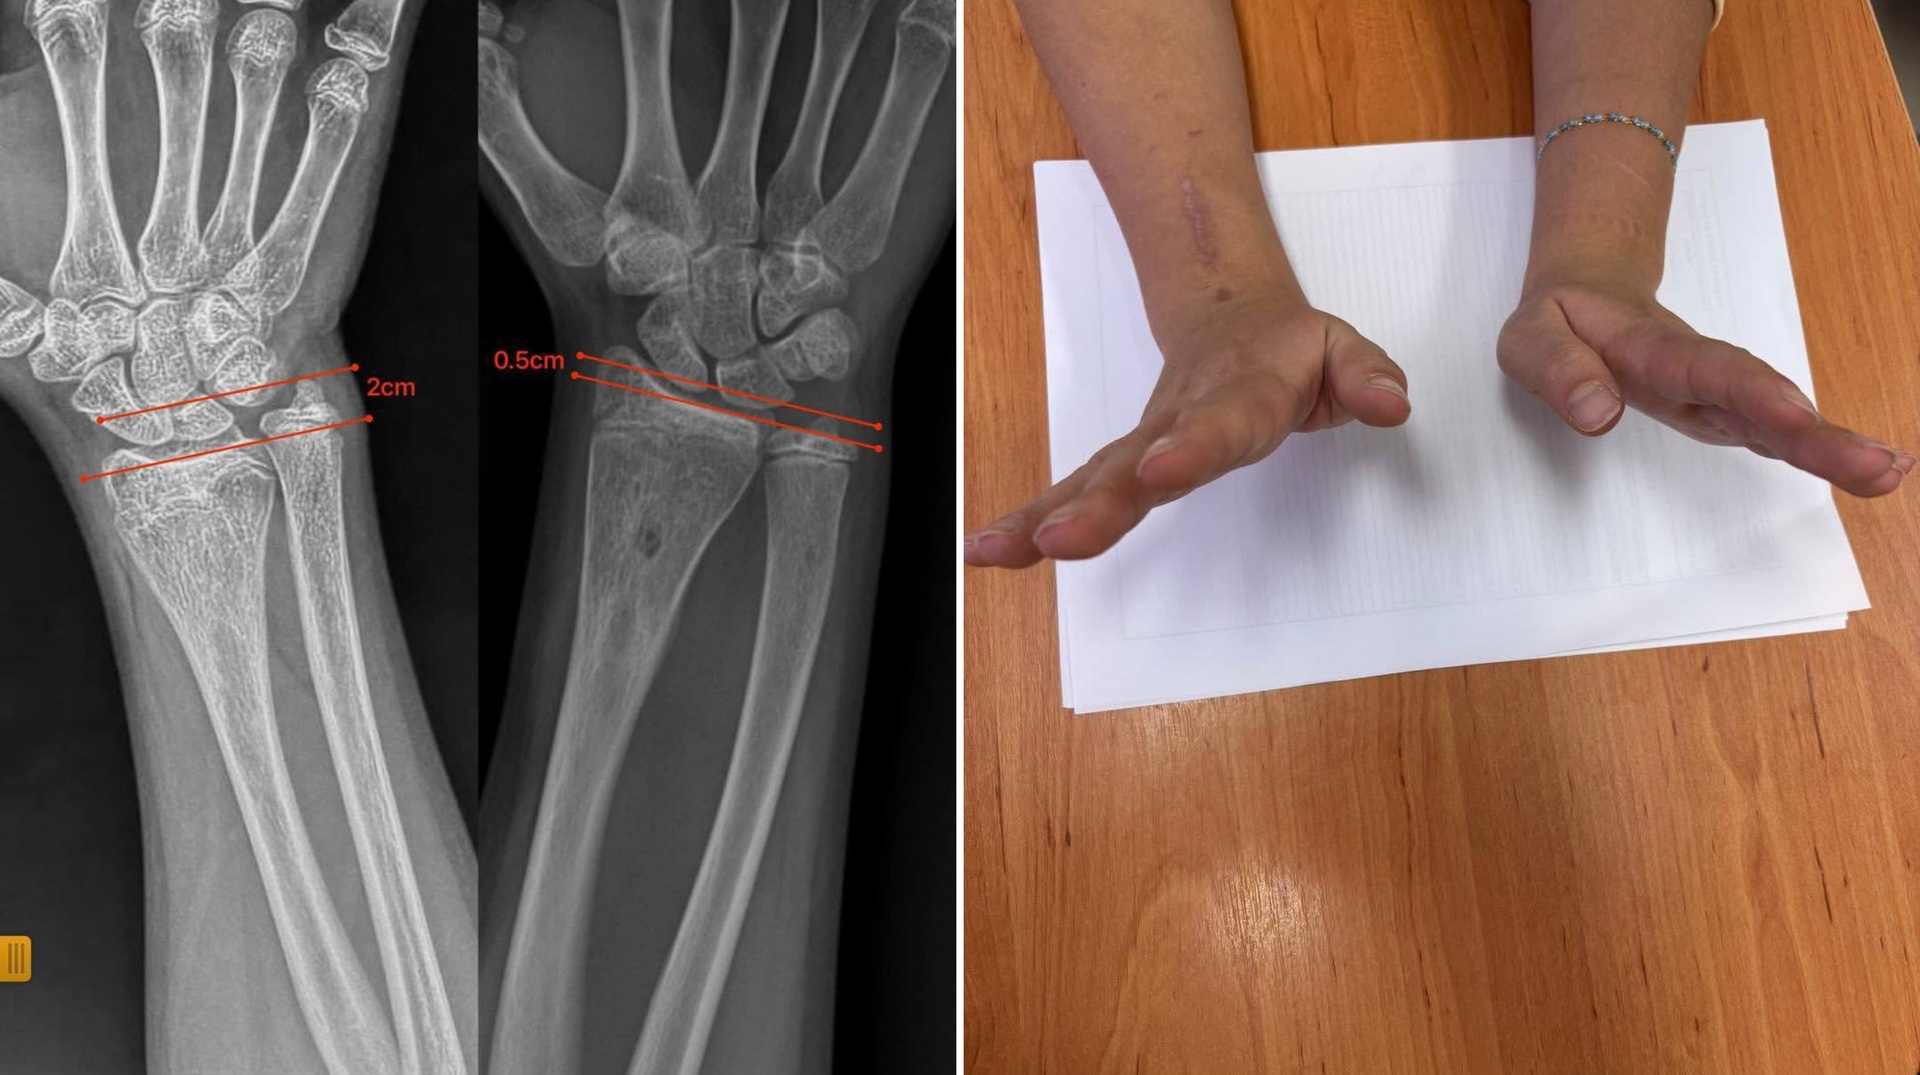

Медики Закарпатської обласної дитячої лікарні провели операцію та видалили кістковий місток, який спричиняв деформацію передпліччя.

Обстеження показало, що ріст однієї з кісток був порушений через утворення кісткового містка, який блокував природний розвиток і спричиняв деформацію.

Під час операції лікарі видалили кістковий місток під контролем ендоскопа. Завдяки такому щадному методу вдалося обійтися без остеотомій та встановлення металоконструкцій — природний ріст кістки відновився самостійно.

Через сім місяців форма передпліччя повністю нормалізувалася, ріст кістки відбувається правильно, а функція кінцівки збережена у повному обсязі.